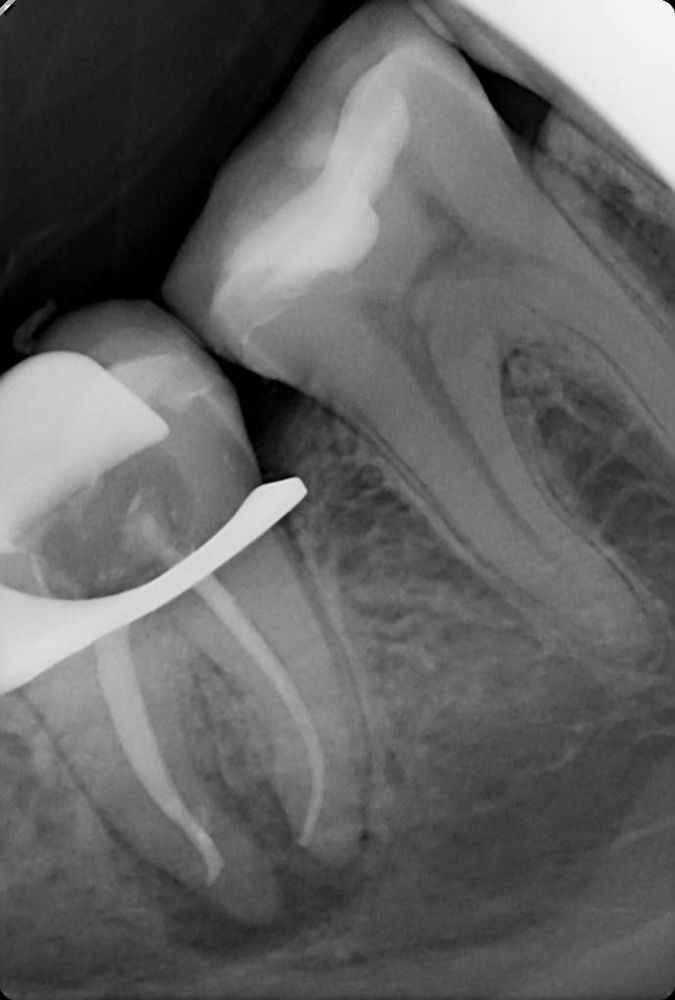

Пациент обратился с жалобами на боль при накусывании на нижний жевательный зуб. Чтобы точно понять причину, мы провели компьютерную томографию (КЛКТ) и обнаружили обширное воспаление костной ткани под корнями зуба, диаметром до 7 мм.

Причина была в гибели сосудисто-нервного пучка зуба: бактерии из корневых каналов проникли в костную ткань и вызвали её разрушение. Без своевременного лечения это могло привести к полной потере зуба и усилению боли.